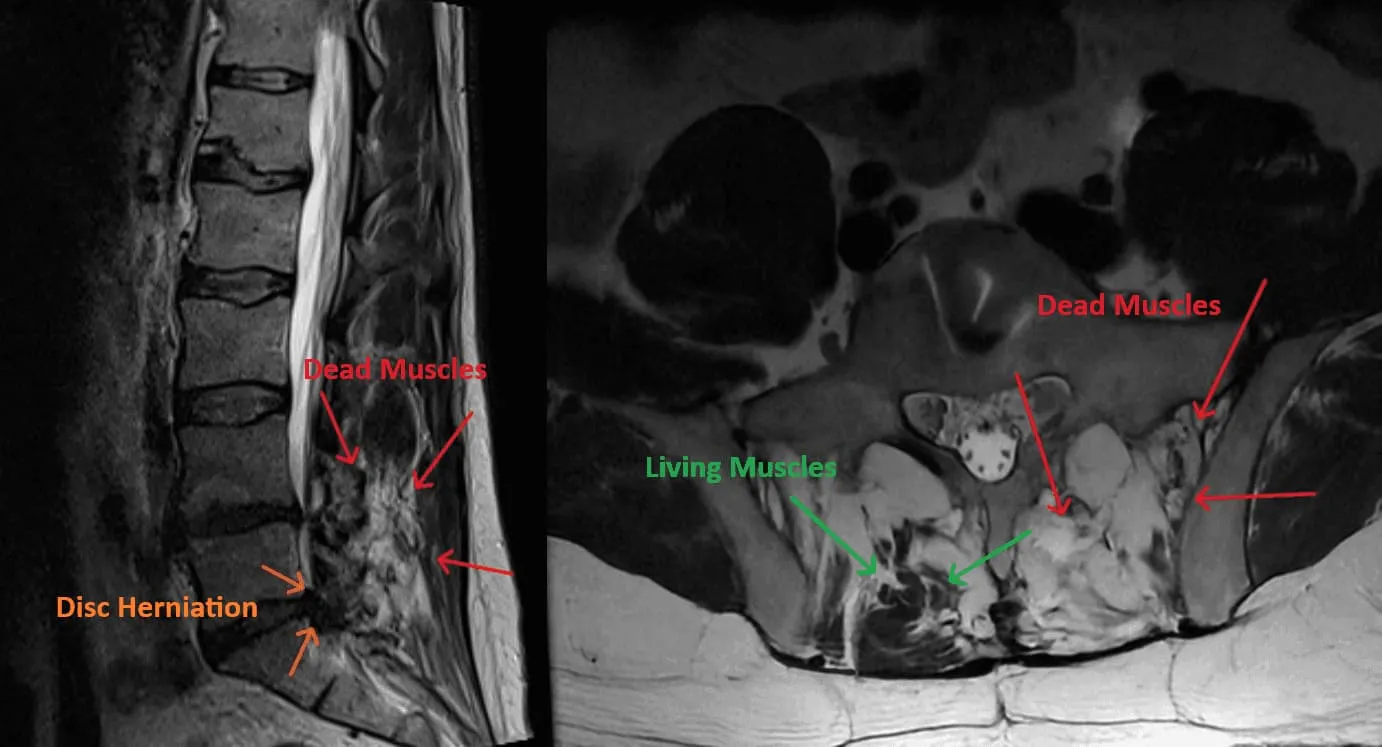

Muscle Destruction

Excessive Scar Tissue

Spinal Instability